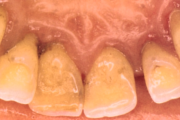

Krooniline parodontiit

Krooniline parodontiit on mikroobide poolt põhjustatud hammaste tugikudede põletik, mille tulemusena tekib progresseeruv alveolaarluu (nähtav röntgenograamil) ja periodontaalligamendi destruktsioon, igemetaskute moodustumine, igeme retsessioon või mõlemad kahjustused kombineeritult. Loe edasi »